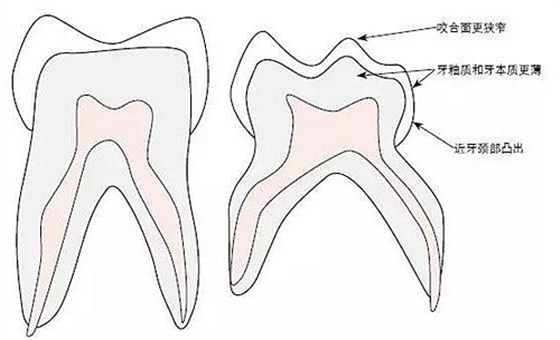

圖1:恒牙(左)與乳牙(右)結(jié)構(gòu)對比示意圖

在兒牙治療中,采取修復(fù)措施時除了上述提到的伴隨情況外,乳牙結(jié)構(gòu)本身也至關(guān)重要。乳牙所具有的宏觀和微觀形態(tài)特征,必須在充填治療時加以考慮(圖1)。首先,與恒牙相比,這個第一牙列的牙齒較小,牙釉質(zhì)和牙本質(zhì)厚度較薄。在這種情況下,牙釉質(zhì)層的厚度小于1mm。這種較低的厚度也意味著乳牙齲齒進(jìn)展起來更加快速。

與恒磨牙相比,乳磨牙表現(xiàn)出明顯的冠形態(tài)差異,這也會對齲齒的形態(tài)有影響。例如,通過乳磨牙平坦的鄰面與鄰牙之間出現(xiàn)不規(guī)則的接觸輪廓。與恒牙接觸點(diǎn)不同,乳牙為鄰間接觸線,當(dāng)牙間隙狹窄時這種接觸方式容易造成鄰面齲。乳牙的其他形態(tài)特征還有牙冠冠向(向)內(nèi)收、近頸部牙釉質(zhì)凸出。在充填治療時,這些特征會增加放置成型片的難度。與恒牙相比,乳牙牙髓腔明顯更大,并且髓角延伸至牙尖處。由于髓腔大,牙釉質(zhì)和牙本質(zhì)層又相對薄,因此為齲洞的預(yù)備留下的空間很小。